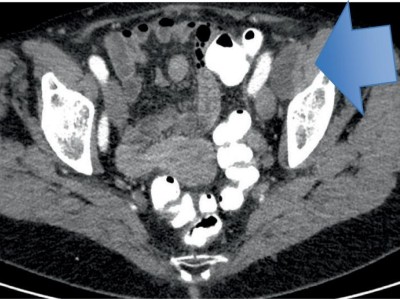

Seltener Befund: Als Skrotalhernie getarnter maligner Tumor

Ein 63-jähriger Patient stellte sich mit einer seit 8 Monaten größenprogredienten Raumforderung im rechten Skrotum ambulant urologisch vor. Er habe keine Schmerzen, sei aber inzwischen deutlich eingeschränkt in der Bewegung und insbesondere beim Sitzen, was seine berufliche Tätigkeit als Baggerfahrer unmöglich mache. Wie lautet Ihre Diagnose?